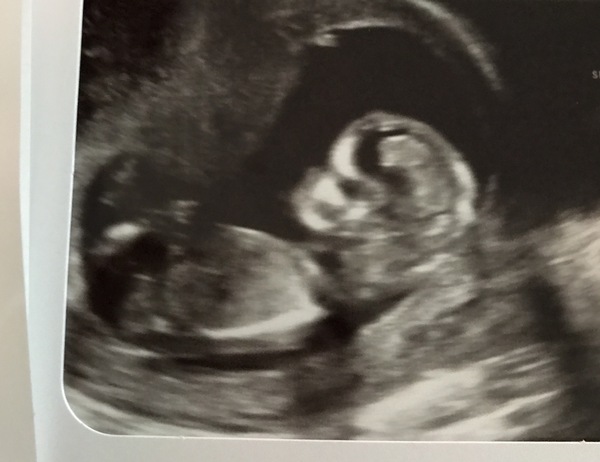

Looking forward to seeing all the posts and pictures! Here’s my little one 💕

@MrsCR2016 thats a lovely pic very clear!

Thank you @scottishem . We were lucky when we went and got a lovley sonography who gave us 2 extra pictures (free too!!) Cant wait for the next one to see him/her

Great pic MrsCR2016!